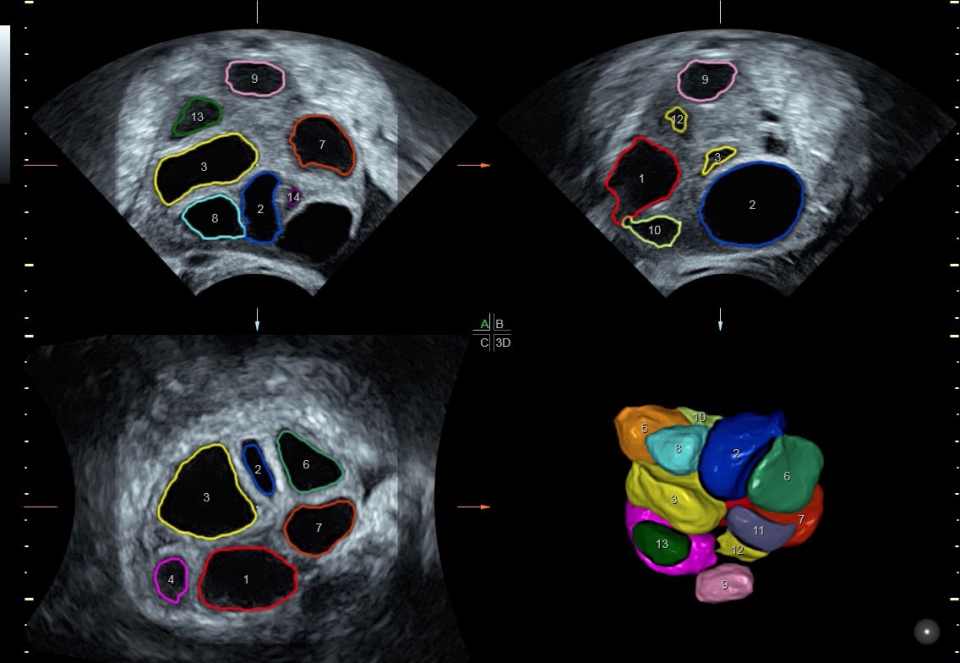

• SonoRenderlive (Автоматическое объемное изображение): Эта функция упрощает получение объемного изображения путем автоматического выбора положения плоскости визуализации для 3D- и 4D-режимов. Это сокращает необходимость вручную настраивать параметры и упрощает процесс получения объемных изображений.

• SonoAVC (Автоматический расчет объема): Эта функция позволяет визуализировать и рассчитывать размеры и объем гипоэхогенных образований, таких как фолликулы яичника или структуры головного мозга плода. Она помогает в оценке этих образований и отслеживании их изменений в течение времени.